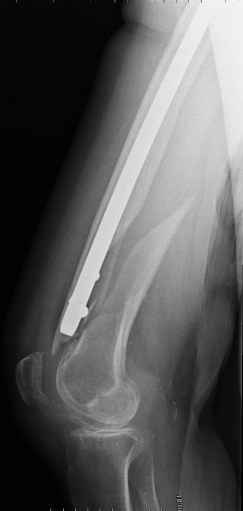

- It is an long, spiral, metaphyseal fracture – very good chance of healing (will not be any need for any bone cement…bone substitute – filler)

- I would use: distal femoral locking plate with few cerclage wires in midsegment and some unicortical locked screws and cerclage wires proximal…

I would consider retrograde femoral interlocking nail after Gamma nail removal during the same surgery.

In my opinion the femoral bone looks osteoporotic, but no bone defect is visible to justify bone cement.

If we have a ready entry point after the gamma removal why perforate the intact knee for another entry - why not just insert a longer antegrade

nail? We definitely would do this. Of course retrograde nailing as well as locked plating would do the job but antegrade nailing in this case is

least invasive among mentioned options.

1. Removal of the nail in elderly, frail lady is not a small procedure (timing and blood loss)

2. It is hard to do "good fixation" of distal fracture through antegrade approach.... and probably distal incision (more than just

for distal locking) would have to be made anyway (reduction, cerclage wires...).

3. Retrograde nail (small diameter in large bone) does not allow for good, stable fixation (often malalignment) and early weight bearing (I have seen the locking screws and nail cutting through the distal femur into the knee joint - in osteoporotic bone, heavy persons)

4. We could treat this fracture like there is no a nail - new locking plates allow for secure fixation.... two similar cases are attached...